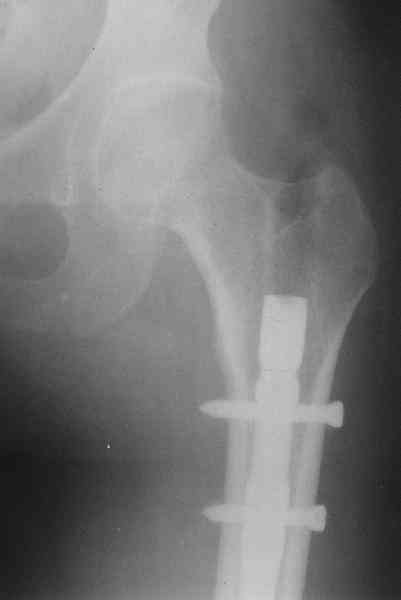

Травма в декабре 2006 года.

Диагноз: Сочетанная травма. ЗЧМТ. Ушиб мозга. Кома.

Закр. перелом левой плечевой кости; левой лучевой кости; оск. перелом

левой бедренной кости.

Оперирована в январе 2007 года по выходу из комы и восстановления

витальных функций. Накостный остеосинтез DCP-LC. Снимки прилагаются.

Через 4 месяца стали беспокоить боли и деформация

бедра. На снимке угловая деформация AP - варус 11 град.; lateral - 29

град. Объем движений в коленном суставе: ограничение сгибания до 90

град. Локально - патологическая подвижность в нижней трети бедра.

Локальная гипертермия, отек мягких тканей. Гиперемии нет.

Передвигалась на костылях.